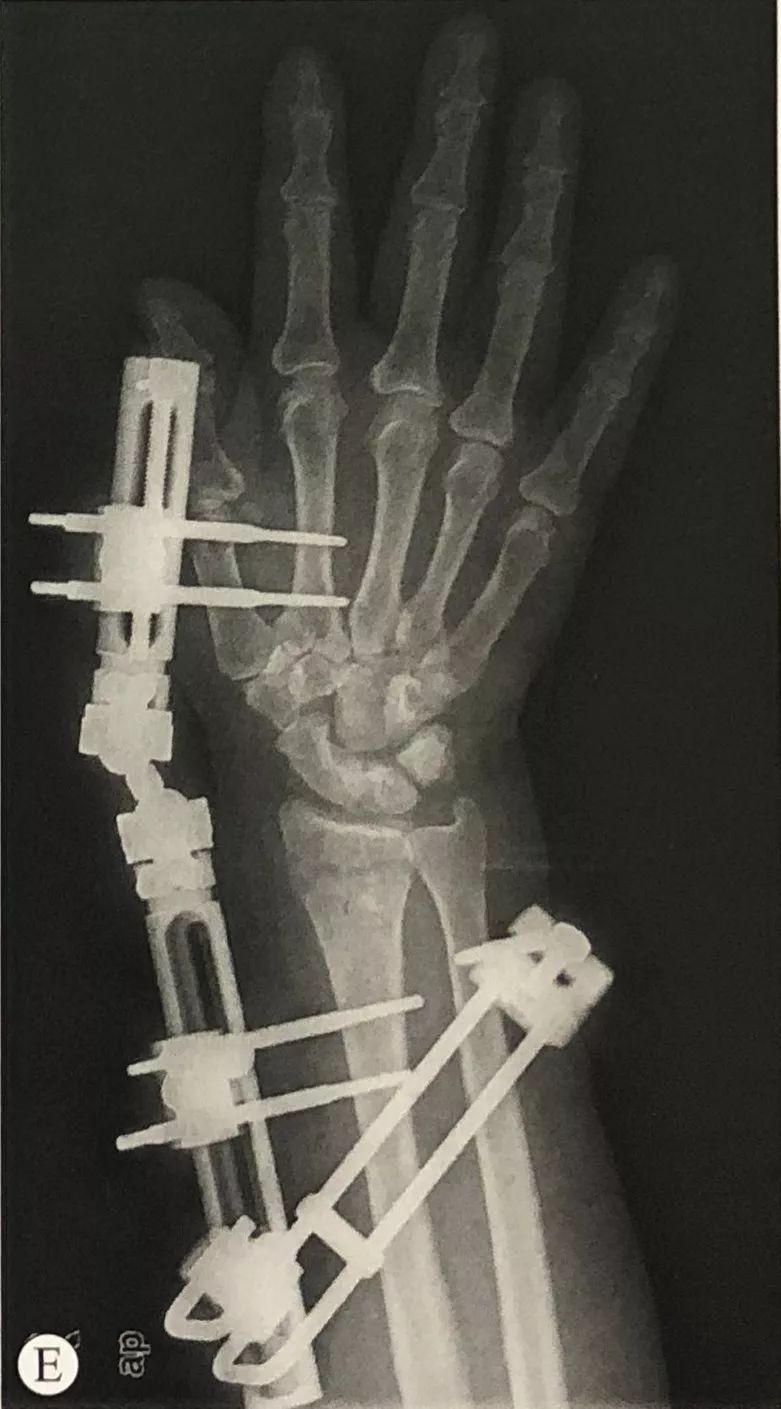

跨关节外固定架固定桡骨远端骨折

• **枚螺钉位于第2掌骨基底部,在示指伸肌腱和第1骨间背侧肌之间,做一皮肤切口,用手术钳轻轻分开软组织,套筒保护软组织,打入1枚3mm Schanz螺钉。

• 螺钉的方向与手掌平面呈45°,也可以与掌平面平行。

• 通过导向器选取第二枚螺钉的位置。在第2掌骨打入第2枚3mm的螺钉。

掌骨固定针的直径不要超过3mm,固定针位置位于近端1/3部,对于骨质疏松的患者,最近端的螺钉可以穿3层皮质(第2掌骨,第3掌骨半侧皮质),这样螺钉固定力臂长、固定扭矩大,增加固定针的稳定性。

桡骨螺钉的置入:

• 与掌骨螺钉在同一平面,套筒保护软组织导向器引导下置入2枚3mm Schanz螺钉。

骨折的复位与固定:

• 手法牵引复位C形臂透视下检查骨折的复位情况。

• 跨腕关节的外固定,难以完全恢复掌倾角,可以结合Kapandji针辅助复位、固定。

• 对于桡骨茎突骨折的患者,可以结合桡骨茎突克氏针固定。

• 维持复位的情况下,连接外固定支架,将外固定架旋转中心同腕关节旋转中心置于同一轴线上。

• 正侧位透视,检查桡骨长度、掌倾角和尺偏角是否恢复,调整固定角度直至骨折复位满意。